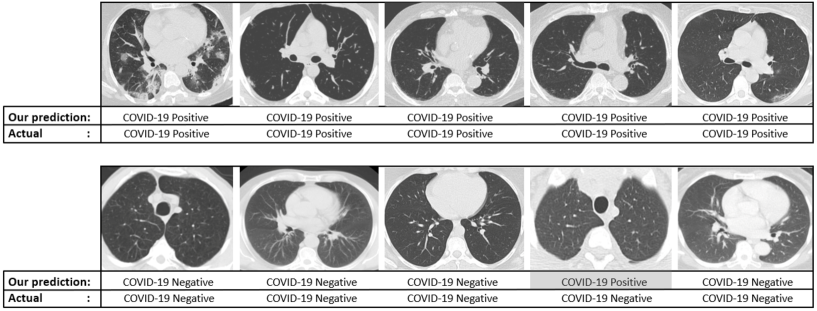

4.2 Robustness Analysis

Machine learning algorithms have achieved persuasive performance in several medical imaging problem but the interpretability of these ML models is very limited and it remains a significant hurdle in adoption of these models in clinical practice. We perform an experiment to check the robustness of our model we perform the following procedures.

In the first stage, we removed critical regions (GGOs and consolidations) of interest from COVID-19 positive cases and then predict its outcome. Secondly, we investigated the performance of our model on images by randomly removing non-COVID-19 regions. We have illustrated some COVID-19 cases in Fig. 17, where we covered the GGOs and consolidations and the model predicted it to be non-COVID-19.

Hence the infected COVID-19 regions are very accurately captured by our chosen topological features and deductively by our model.